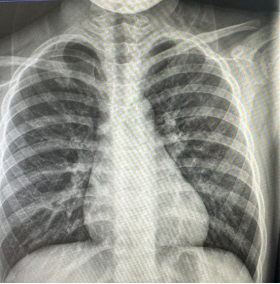

朱某,男,2016-3-15出生,因“跌倒致左肩疼痛伴活动受限2小时”2019年12月12日来我院门诊。检查发现左锁骨区见肿胀、畸形,明显压痛,左肩活动受限。本院X线摄片示:左锁骨骨折,断端明显重叠移位(图1),予以8字绷带外固定制动,定期随访。2020年1月17日复诊述左肩无肿痛,活动基本正常,摄片示:左锁骨骨折,断端对线欠佳,局部明显骨痂形成(图2)。2020年6月8日再次复查摄片示:左锁骨骨折,断端对线可,已骨性愈合(图3)。2023年9月26日再复查摄片示:左锁骨骨折部位已完成塑形,与健侧无明显差异(图4)。

图4